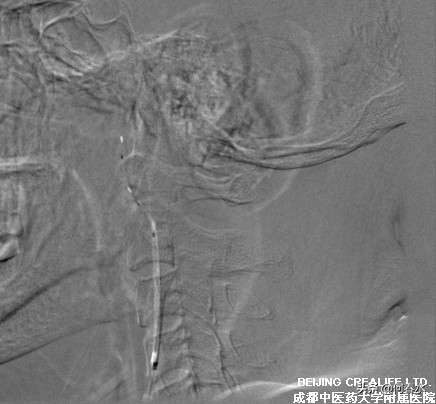

影像资料如下:

图片说明:造影显示,颈内动脉起始段重度狭窄,狭窄率达95%

图片说明:在远端保护伞的情况下,送入支架

图片说明:支架植入后,狭窄完全消失,远端保护伞随后取出